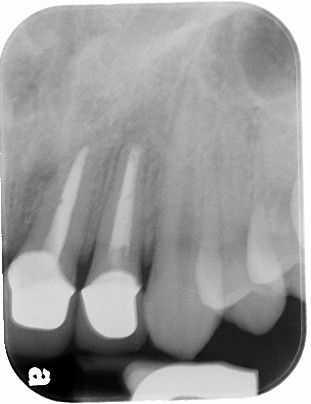

圖十四為手術後的X光片,可見根尖逆充填及根尖囊腫,都已完全處理,經過6個月後,牙根的破壞已完全癒合(圖十五),可繼續進行瓷牙重建。